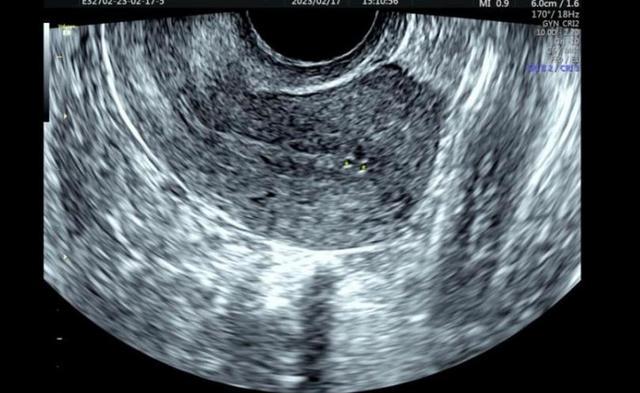

二维超声:内膜中上段回声中断,厚薄不均。

二维超声:子宫内膜菲薄,并可见多处少量局限性积液。